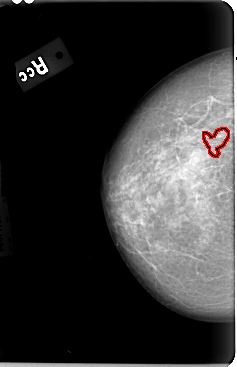

B_3030_1.RIGHT_CC

FILE: B_3030_1.RIGHT_CC.OVERLAY

TOTAL_ABNORMALITIES 1

ABNORMALITY 1

LESION_TYPE CALCIFICATION TYPE PLEOMORPHIC-FINE_LINEAR_BRANCHING DISTRIBUTION CLUSTERED

ASSESSMENT 4

SUBTLETY 3

PATHOLOGY BENIGN

TOTAL_OUTLINES 1

BOUNDARY